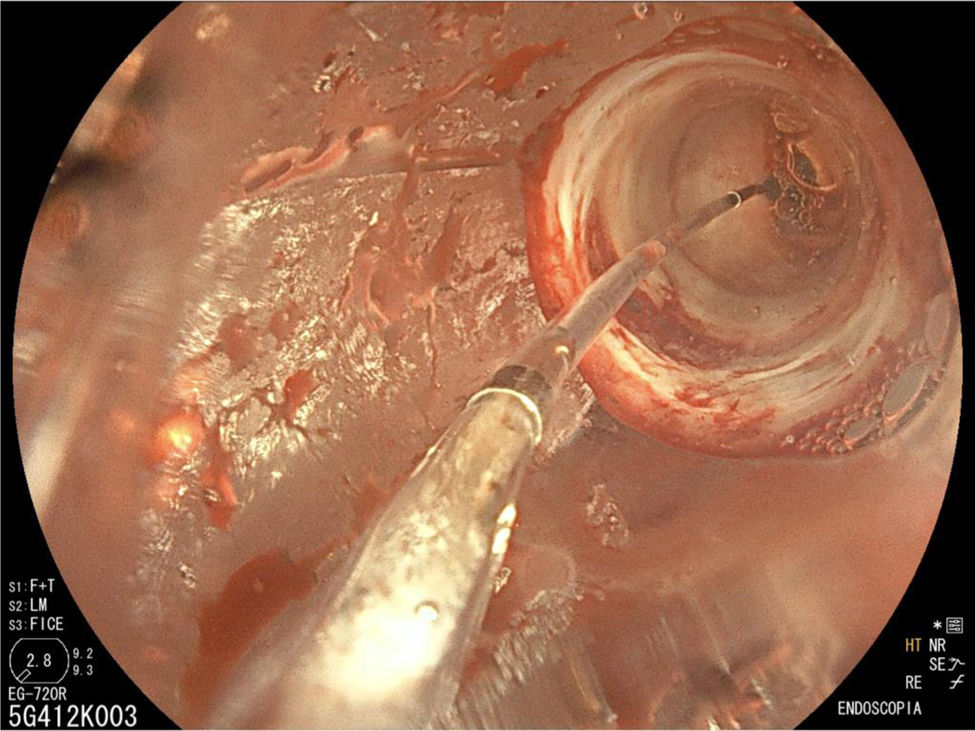

The endoscopy revealed a narrowing of the pylorus that prevented the endoscope from entering the duodenum (Fig. 1), leading to performance of hydrostatic balloon dilation (Figs. 2 and 3). The analysis of the biopsy specimens led to diagnosis of gastritis associated with Helicobacter pylori infection and foveolar hyperplasia.